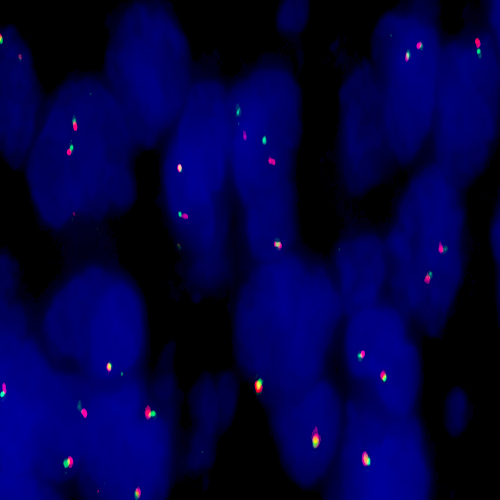

Human thyroid: immunohistochemical staining for Thyroid Transcription Factor-1. Note nuclear staining of thyroid epithelial cells. Thyroid Transcription Factor-1: clone SPT24

Thyroid Transcription Factor-1 (TTF-1) is a member of the homeodomain transcription factor family and plays a role in regulating genes expressed within the thyroid, lung and brain. These include thyroglobulin, thyroid peroxidase, Clara cell secretory protein and surfactant proteins. Human TTF-1 (38 kD) is a single polypeptide of 371 amino acids sharing 98% homology with the equivalent rat and mouse proteins. TTF-1 functions by binding to specific recognition sites in a manner that may be regulated by both the redox and phosphorylation status of the protein. In addition to its role as a tissue-specific transcriptional activator in adult organs, TTF-1 may also function in organogenesis. Gene targeting studies have shown TTF-1 to be essential for the proper development of the thyroid and lungs and abnormal expression may underline a number of congenital abnormalities.